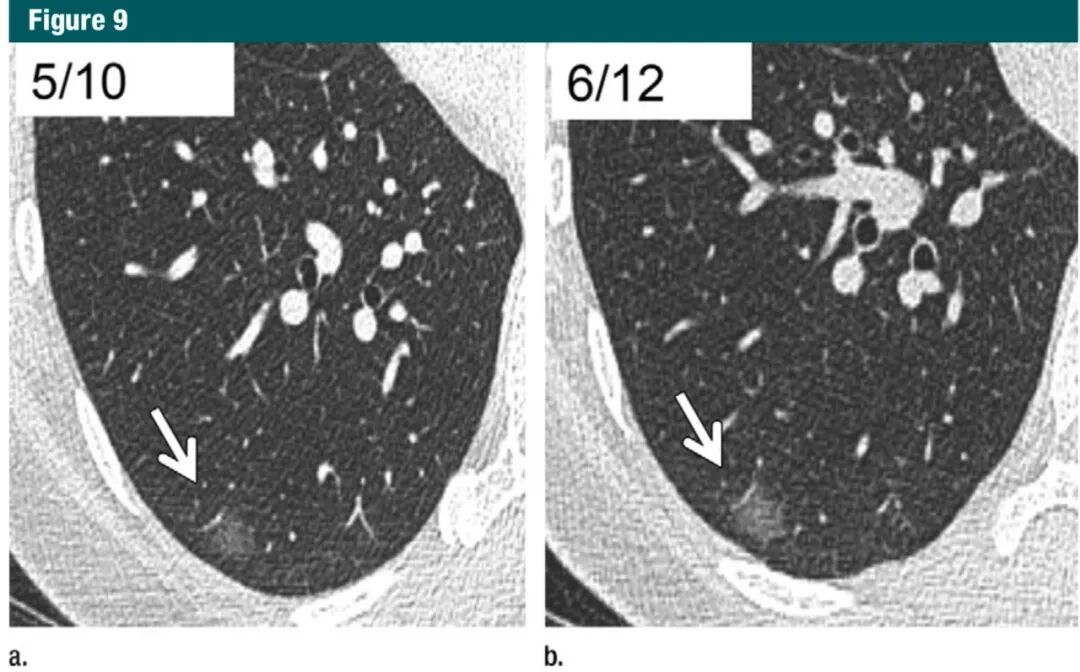

目前,大量文献研究结果显示≥6mm的纯磨玻璃结节随访5年是安全的,通常经过3-4年即可确诊该结节是否增大,仅有少数病例发展诊断为浸润性癌(图9,10)。

图9:横断位1mm CT层面,含右下叶。a:显示一个边缘清晰的6mm磨玻璃结节(箭头);b:在图a之后超过2年后随访,显示病灶稍增大(箭头),这个发现因邻近血管结构的轻微改变得出来的。这种轻微改变仅能通过1mm连续薄层扫描发现,符合原位腺癌或微浸润腺癌,推荐继续每年随访。7Gc帝国网站管理系统